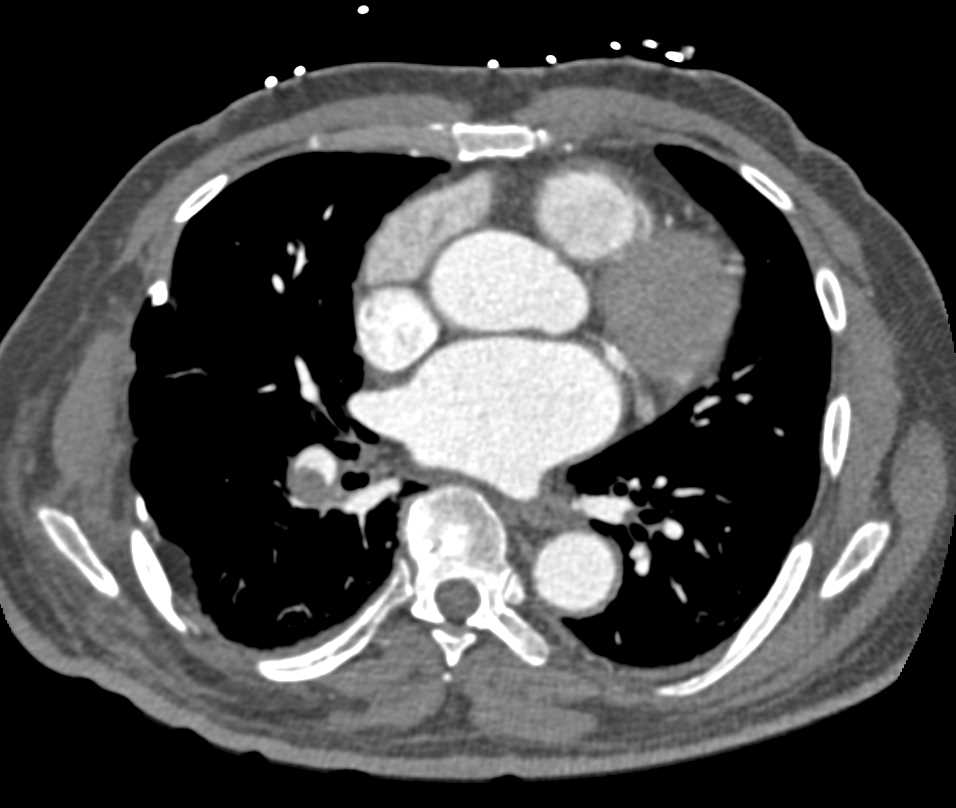

Pulmonary Embolism with Rectal Impaction